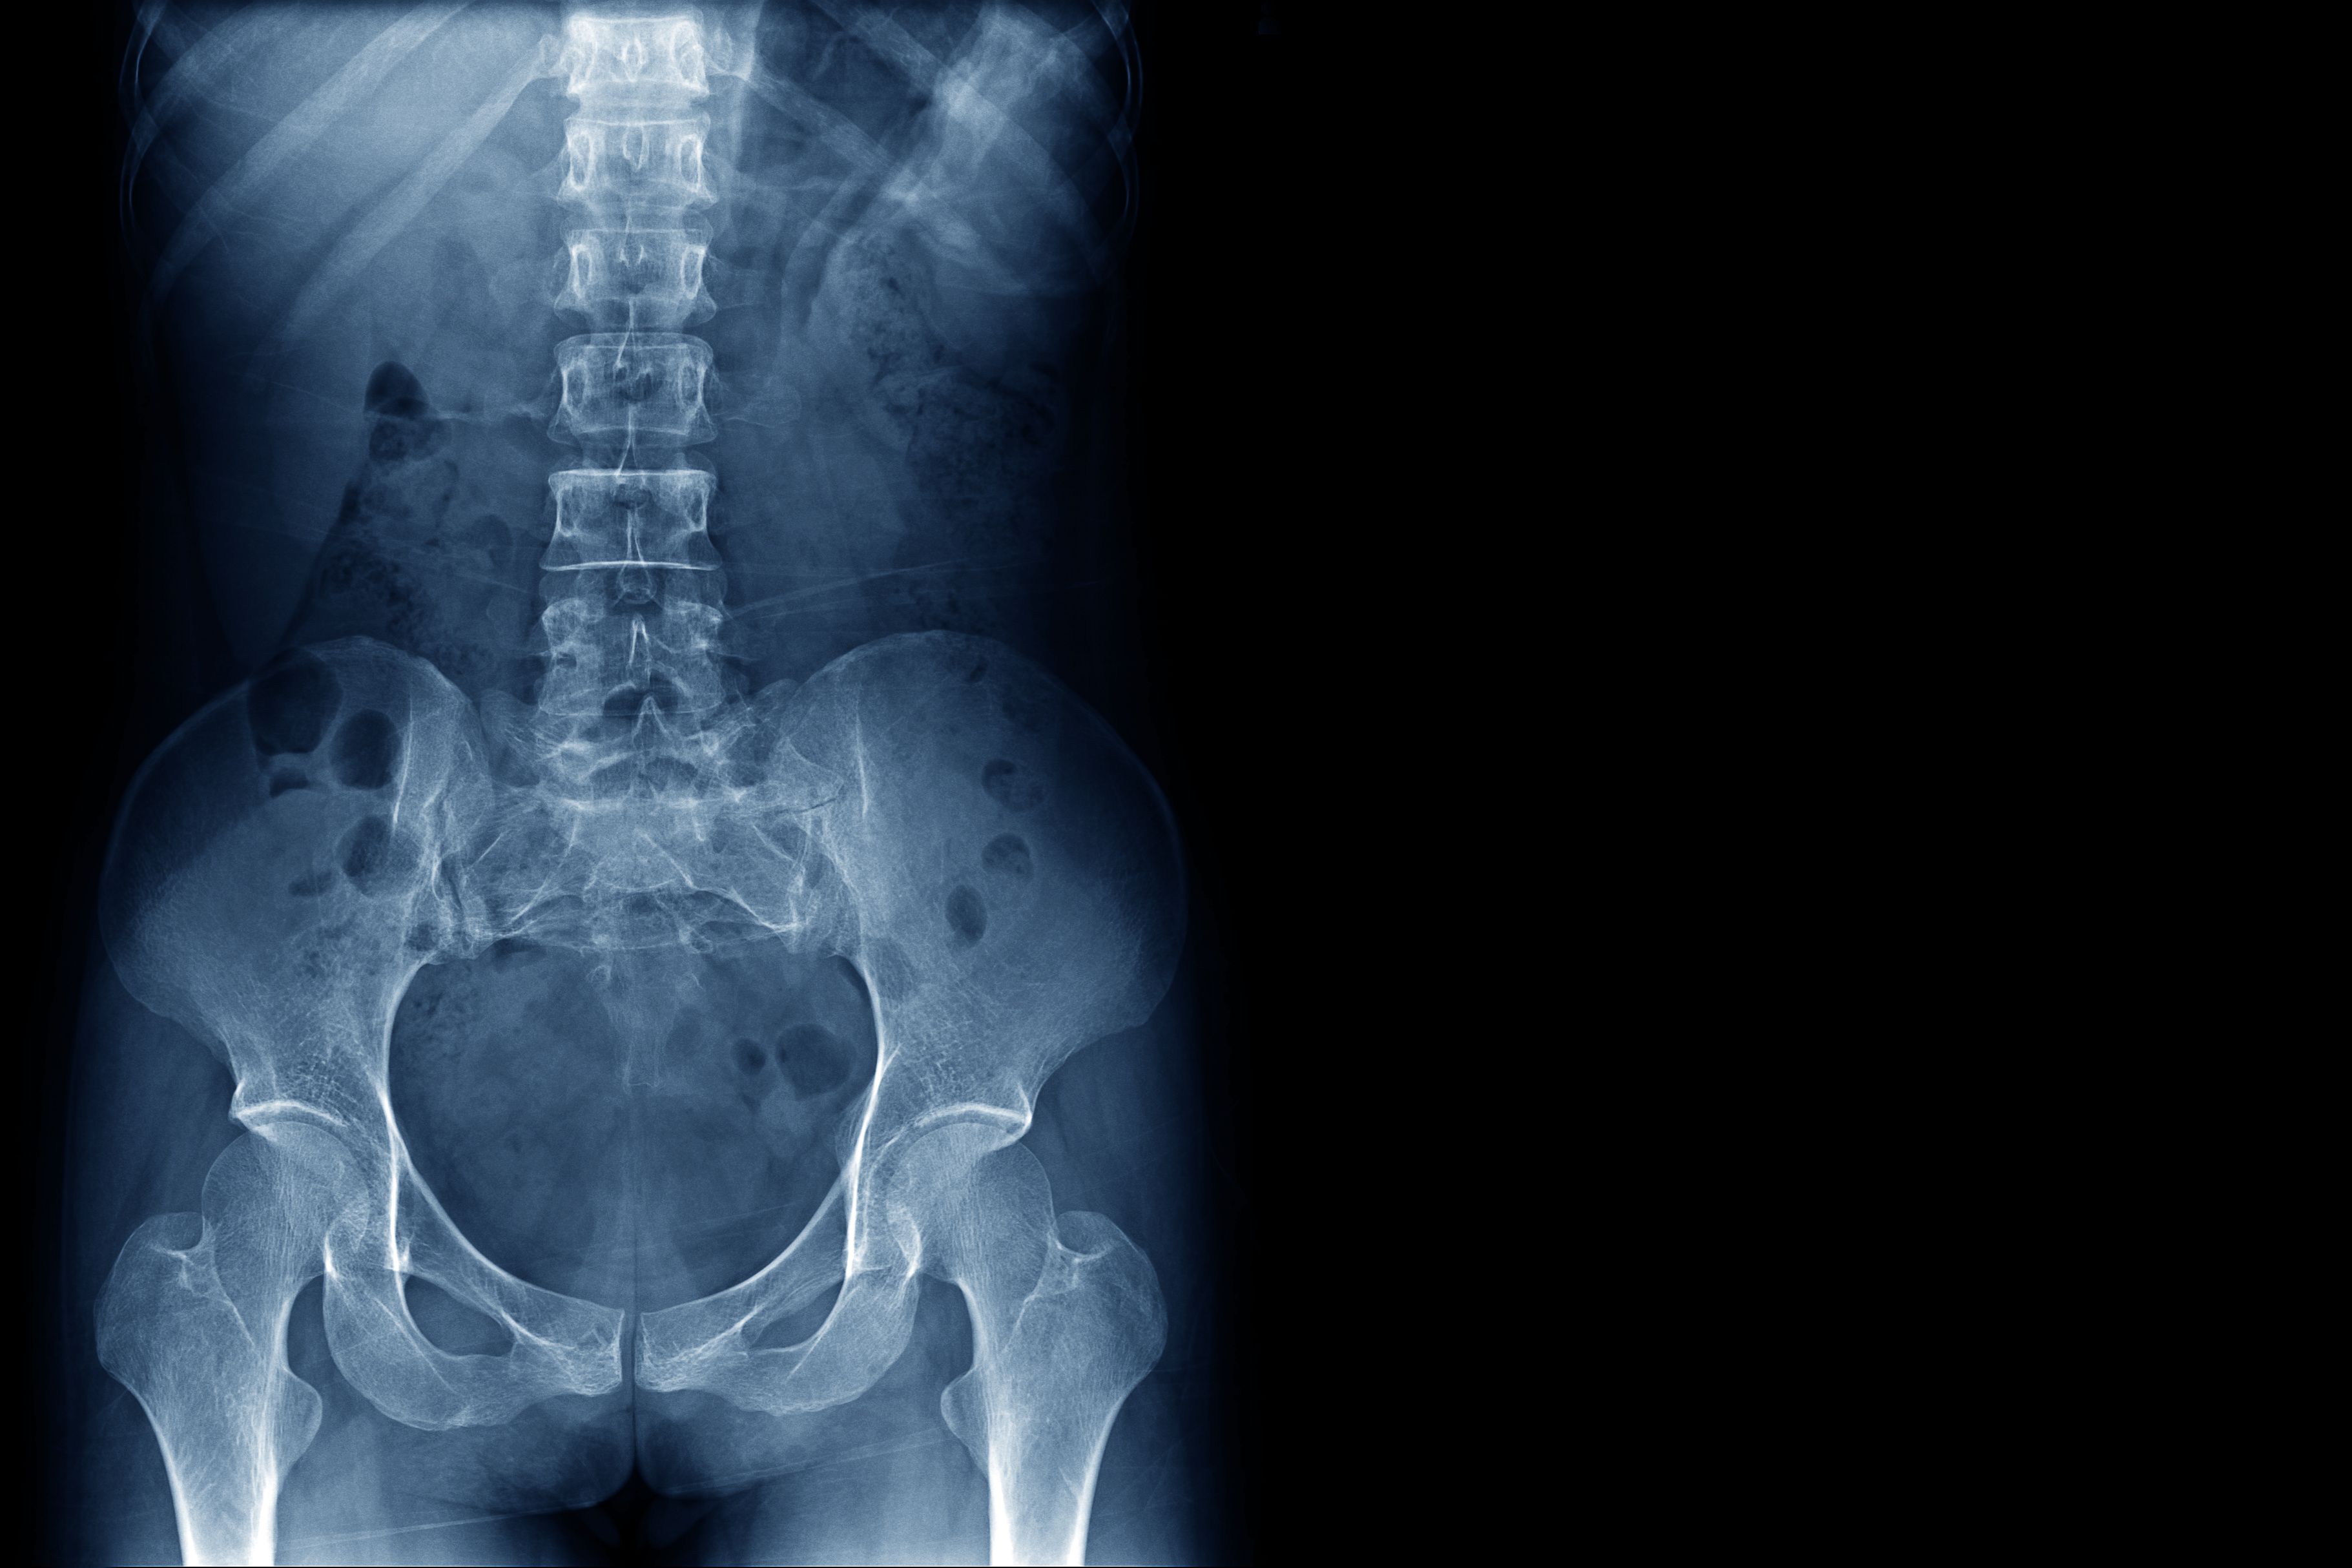

NonRadiographic Axial Spondyloarthritis (nraxSpA) Diagnosis Symptoms Upadacitinib Non-Radiographic Axial Spondyloarthritis Upadacitinib 15 mg was efficacious and well tolerated in patients with active ankylosing. tofacitinib and upadacitinib, an inhibitor of jak1, are effective in controlling disease activity in radiographic axial spondyloarthritis. Food & drug administration (fda) approved upadacitinib, a janus kinase (jak). Upadacitinib Non-Radiographic Axial Spondyloarthritis.

What Is NonRadiographic Axial Spondyloarthritis (nrAxSpA)? Upadacitinib Non-Radiographic Axial Spondyloarthritis tofacitinib and upadacitinib, an inhibitor of jak1, are effective in controlling disease activity in radiographic axial spondyloarthritis. Upadacitinib 15 mg was efficacious and well tolerated in patients with active ankylosing. Food & drug administration (fda) approved upadacitinib, a janus kinase (jak). Upadacitinib Non-Radiographic Axial Spondyloarthritis.

What Is Nonradiographic Axial Spondyloarthritis? Upadacitinib Non-Radiographic Axial Spondyloarthritis Upadacitinib 15 mg was efficacious and well tolerated in patients with active ankylosing. tofacitinib and upadacitinib, an inhibitor of jak1, are effective in controlling disease activity in radiographic axial spondyloarthritis. Food & drug administration (fda) approved upadacitinib, a janus kinase (jak). Upadacitinib Non-Radiographic Axial Spondyloarthritis.

Axial Spondyloarthritis vs. Ankylosing Spondylitis What's the Difference? Upadacitinib Non-Radiographic Axial Spondyloarthritis tofacitinib and upadacitinib, an inhibitor of jak1, are effective in controlling disease activity in radiographic axial spondyloarthritis. Food & drug administration (fda) approved upadacitinib, a janus kinase (jak). Upadacitinib 15 mg was efficacious and well tolerated in patients with active ankylosing. Upadacitinib Non-Radiographic Axial Spondyloarthritis.

Non Radiographic Axial Spondyloarthritis Comprehensive Guide Upadacitinib Non-Radiographic Axial Spondyloarthritis Food & drug administration (fda) approved upadacitinib, a janus kinase (jak). tofacitinib and upadacitinib, an inhibitor of jak1, are effective in controlling disease activity in radiographic axial spondyloarthritis. Upadacitinib 15 mg was efficacious and well tolerated in patients with active ankylosing. Upadacitinib Non-Radiographic Axial Spondyloarthritis.